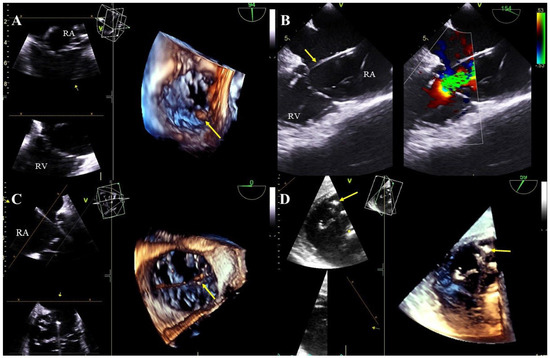

Lead-dependent tricuspid valve dysfunction (LDTVD): new valve regurgitation caused by the lead. The most common mechanism is impingement of the valve, adhesion of the lead to the leaflet or its perforation during implantation (Figure 4A–D, Movie S7).

Figure 4. Tricuspid valve dysfunction caused by the presence of the electrode (TEE 2D, 3D). The lead (yellow arrow) in the tricuspid valve supports the septal leaflet and hinders proper coaptation of the leaflets (TEE 3D) (A,C). Severe tricuspid valve regurgitation resulting from the septal leaflet being pathologically supported by the lead (yellow arrow), (2D, color Doppler image from panel A) (B). The posterior leaflet of the tricuspid valve is perforated by the lead (yellow arrow) (D).